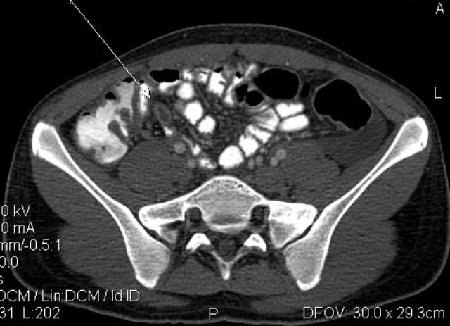

- Острый аппендицит, КТ MPR coronal

- AA Cor.jpg (18.44 КБ) 1340 просмотров